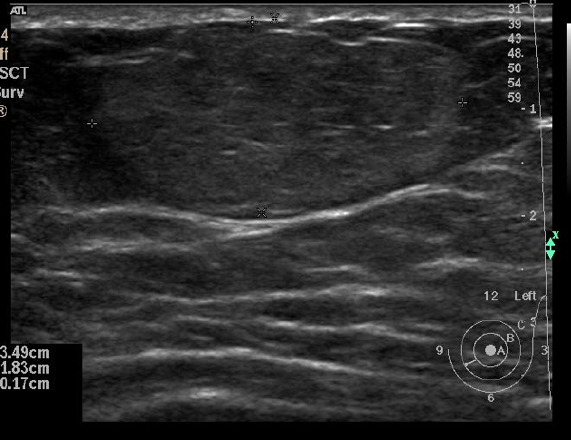

Normal breast US appearance

• Tissue

• Premammary zone (hypoechoic)

• Mammary zone (hyperechoic)

• Retromammary zone (hypoechoic)

• Pectoralis major (hyperechoic)

• Cooper’s ligament (hyperechoic bands)

• Course oblique through subcutaneous fat

• Ducts

• Collapsed (central bright echo)

• Mildly ectatic (2 hyperechoic lines, anechoic lumen)

• Severely ectatic (2 further separated hyperechoic lines)

• TDLUs

• ~2mm hypoechoic structures

• Larger with adenosis + pregnancy